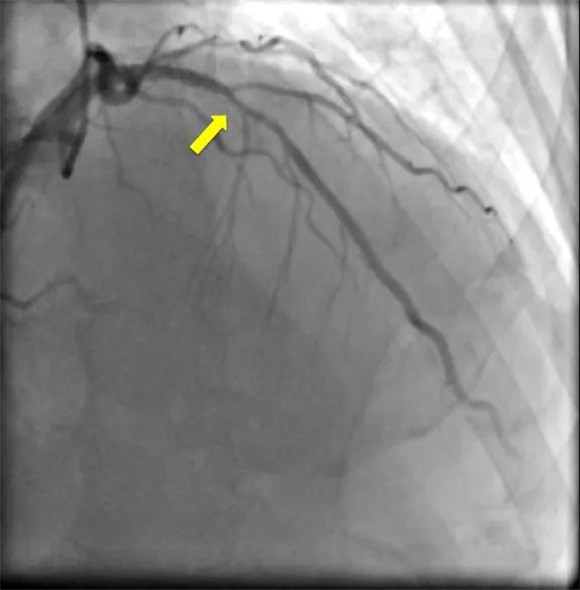

62岁的于大妈是个老病号了,不仅患有高血压和高血脂,而且还有严重的哮喘病,一年内就因为哮喘急性发作反复住了好几次医院;更不幸的是,这两年于大妈又添了个胸痛的毛病,虽然吃了不少药,可是胸痛的症状却越来越重,每次都要持续十来分钟才能缓解。于是,她慕名来到了北医三院心内科,冠状动脉造影发现,于大妈冠状动脉中的前降支狭窄了70%。

冠状动脉造影

要想判断冠脉临界病变是否会导致心肌缺血,传统的方法是在冠脉造影过程中用压力导丝检测FFR,但这种技术需要通过肘部的大静脉高速输注一种扩张微血管的药物ATP,不仅操作费时,而且这种药物可能诱发哮喘发作、心动过缓或低血压,因此患有严重哮喘的于大妈不能采用FFR技术。

iFR是一种使用压力导丝在冠状动脉造影术中进行的用于明确冠脉临界病变是否会导致心肌缺血的检测方法,用于指导冠脉临界病变是否需支架治疗。检测时仅需将一条压力导丝送入冠状动脉即可立即得到检测结果。

iFR检测